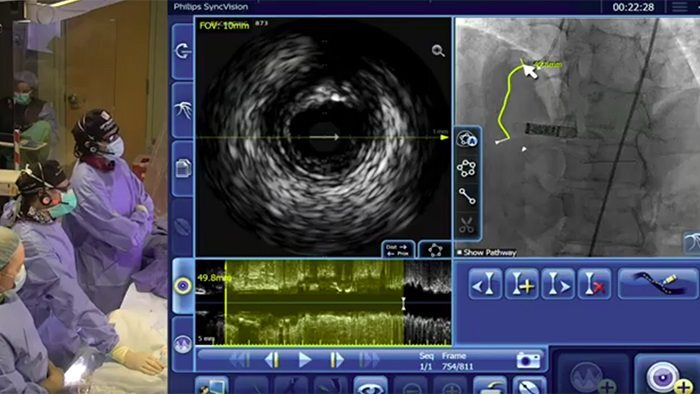

Asigne los valores de iFR directamente al angiograma, de modo que pueda ver con precisión qué partes de un vaso están produciendo la isquemia

Disponible en la nueva plataforma de aplicaciones intervencionistas Philips IntraSight y como actualización a los sistemas Core.

El Dr. Allen Jeremias explica la necesidad de entender no solo si hay isquemia, sino dónde está al planificar la ICP

Presentación de la plataforma de todas las nuevas aplicaciones intervencionistas IntraSight de Philips, donde la adquisición de imágenes, la fisiología, el corregistro10 y el software se unen para facilitar la atención óptima del paciente. IntraSight ofrece un paquete integral de modalidades clínicamente comprobadas, como iFR/FFR, IVUS y corregistro10, para simplificar intervenciones complejas, acelerar procedimientos de rutina y proporcionar una mejor atención al paciente.

10. Herramientas de corregistro disponibles en la configuración de IntraSight 7 mediante SyncVision.